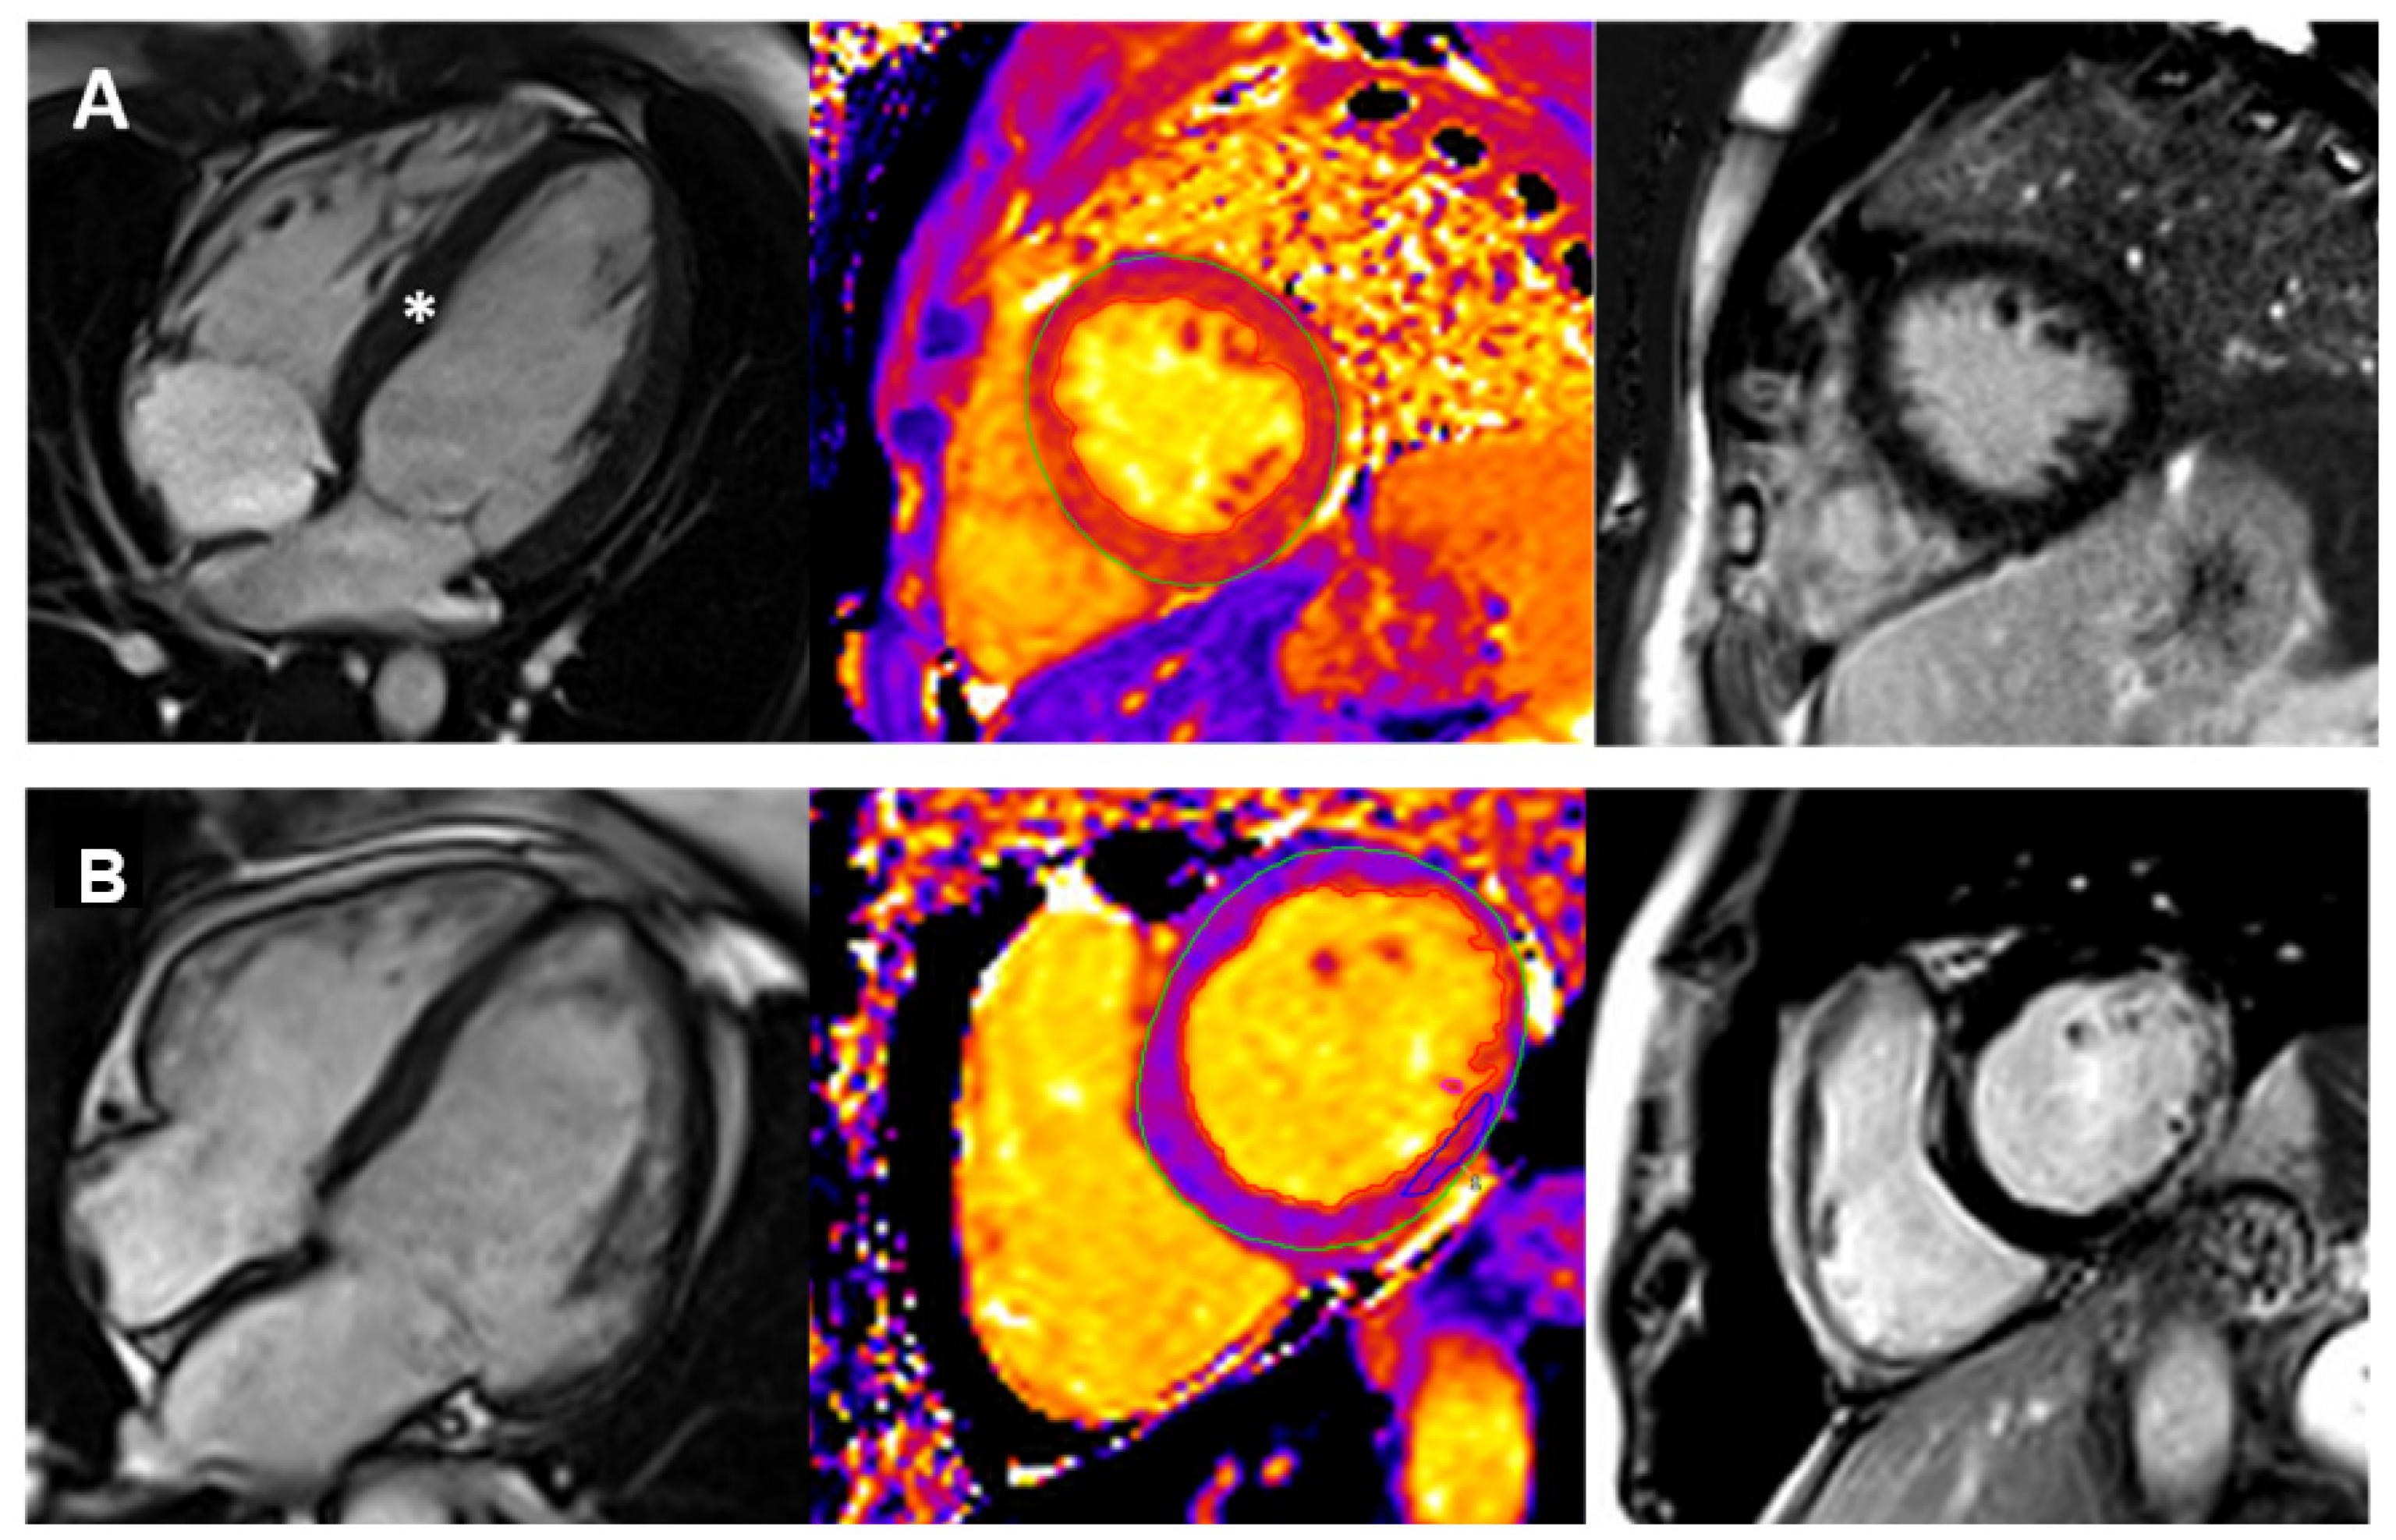

3.2. CMR Application in Paediatric Cardiomyopathies

3.1.4. Native T1,T2 Mapping

3.1.5. Late Gadolinium Enhancement (LGE)